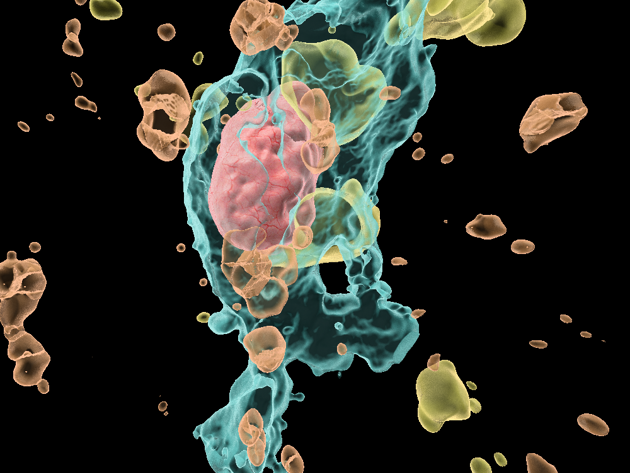

Figuur B - 3D model vet-geladen macrofaag in glioblastoom die myeline opneemt

Figuur B

Een 3D model van een vet-geladen macrofaag (blauw is het cellichaam, rood de kern) in een glioblastoom bij een muis die myeline opneemt (geel).

Na de opname van de myeline worden de vetten hergebruikt en bewaard in vet druppels (oranje).